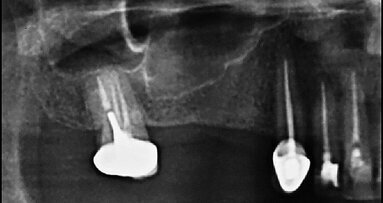

Yoshi navrhnul dvě krásné „mikrolžičky“ – Micro-spoon koncovky (obr. 2), které používá k vytvoření „cesty“ mezi nástrojem a vnitřní plochou ohbí. Tyto koncovky v TFRK setu jsou obrácené k („6 hodin” koncovka) nebo proti („12 hodin“ koncovka) ultrazvukovému násadci. Volíme je podle směru zakřivení kanálku. Pozice koncovky při práci pak naléhá na vnitřní stěnu ohbí vedle odděleného nástroje.

Všechny ultrazvukové koncovky TFRK jsou vyrobeny z měkké nerezavějící oceli, jsou výrazně prodloužené, což umožňuje jejich snadné „předehnutí“, ale jsou citlivé k předčasnému zlomení při nevhodné manipulaci. Přiměřený výkon na ultrazvukovém unitu se pohybuje typicky v dolní čtvrtině škály. Doporučeno je aktivovat raději přerušovaně, „poklepáváním” nožního spínače než kontinuálním spuštěním. Přerušovaná aktivace chrání koncovku před přehřátím a zprostředkuje relativně silný impulz skrze tenký dlouhý nástroj. Po dvou až třech impulzech koncovku vyjímáme a kontrolujeme případné poškození, přičemž se koncovka ochladí. Vyčistíme koncovku pomocí alkoholu na houbičce a pokračujeme v další práci, než dojde k uvolnění nástroje. Kontinuální práce ultrazvukové koncovky v oblasti ulomeného fragmentu také zvyšuje riziko jeho rozlomení do menších částí.